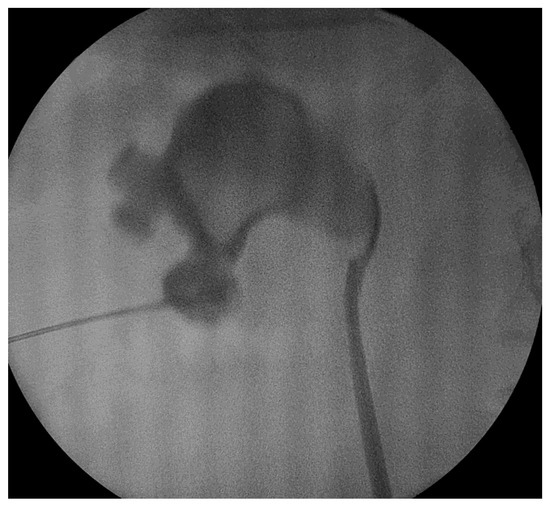

The stone was located in either one single calyx or just extending to the renal pelvis and the stone size was less than 20 mm in its maximal diameter. The intrarenal stone location was as follows: upper calyx in 7 cases, middle calyx in 20 cases and lower calyx in 46 cases, while 29 patients had a renal pelvis stone. The male to female ratio was 1.5:1, and the mean age was 48.4 years old. The stone size was measured on the longest axis on preoperative imaging. The mean stone size was 17.4 mm in diameter (ranging between 9 and 20 mm) (Figure 3). In cases where a CT scan was available, we measured a median value of about 900 HU, ranging from 740 to 1290 HU.

Figure 3. Stone fragments after mini-perc technique.